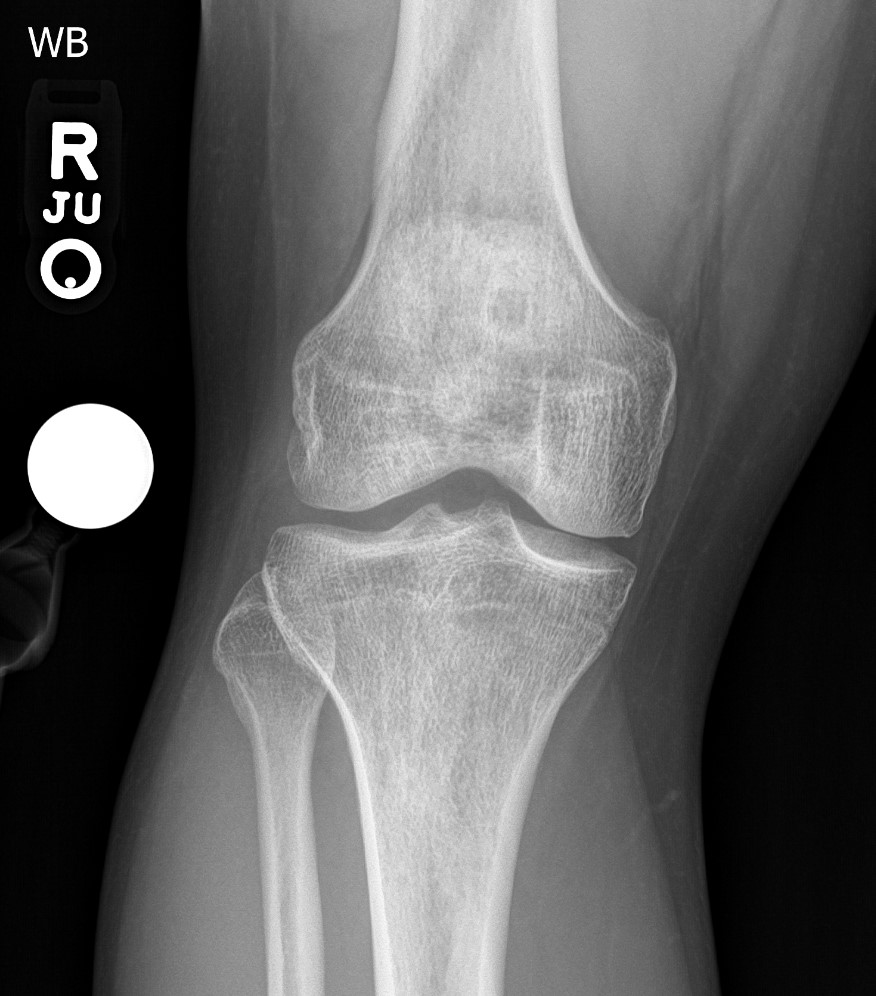

melorheostosis (rid34660)

by bjoern jobke, md ( 3.67 )